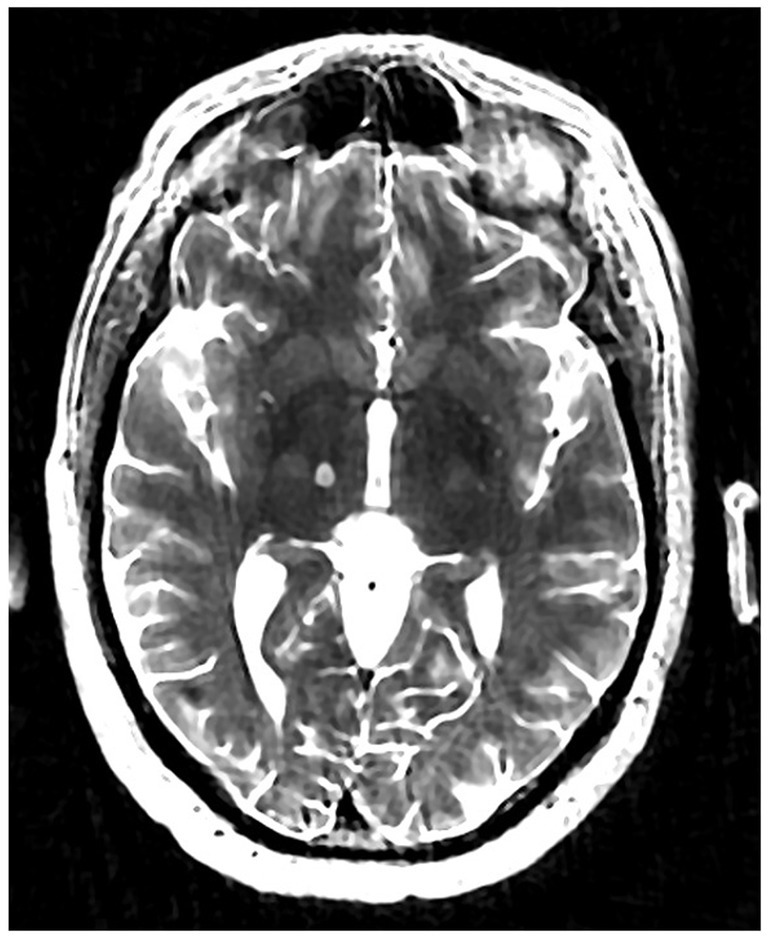

The patient underwent MRgFUS thalamotomy targeting right VIM to treat the dominant left-hand tremor (Figure 3). The ablative temperature was reached with high-intensity focused ultrasound (HIFU) sonication with real-time MR guidance and clinical assessment. Tremor response and adverse effects were assessed between sonication.

Figure 3

Volumetric T2-weighted image showing right VIM MRgFUS thalamotomy lesion.